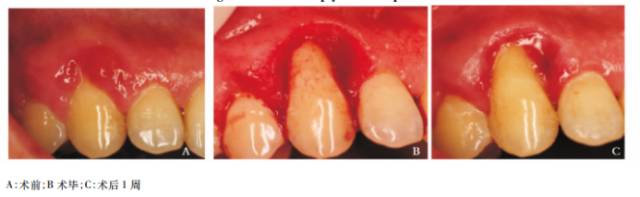

排龈法是牙体修复常用的手段,激光用于排龈创伤小,出血少,速度快~冠延长术和残根保存治疗中激光也能派上用场~陈峰等利用水激光进行前牙美容性冠延长术术中无需翻开黏骨膜瓣,只需将特定的光纤伸入龈沟内即可进行牙槽骨的修整,简化了手术步骤,不翻瓣,牙龈及牙槽骨术后更加稳定,如果涉及到修复, 其修复时间从传统的8周缩短到6周(陈峰,等。2013.)。